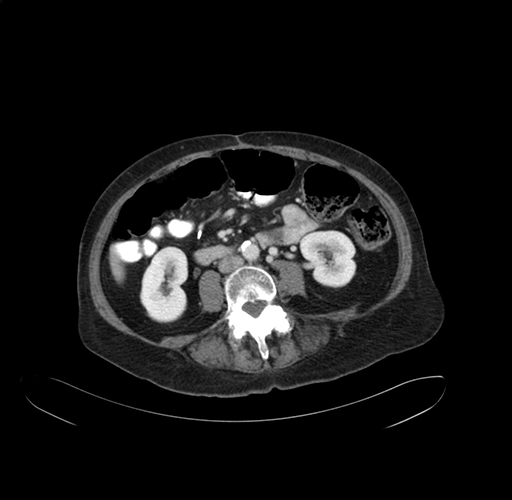

Pre-Chemo: Axial Venous

Axial Venous